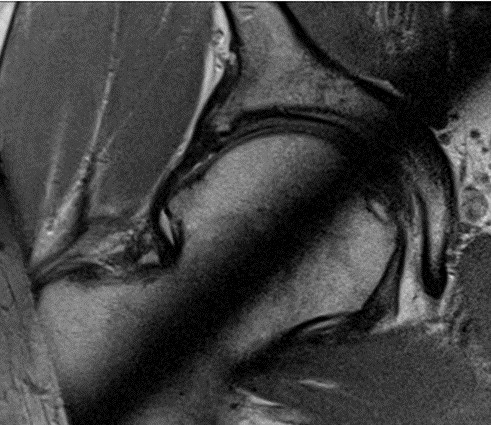

Dziecko w wieku 5 lat i 9 miesięcy zgłosiło się do ortopedy z powodu dolegliwości bólowych lewego stawu kolanowego i okresowych dolegliwości bólowych lewego stawu biodrowego. W badaniu klinicznym stwierdzono niewielkie ograniczenie ruchów odwodzenia w stawie biodrowym i rotacji do wewnątrz. Podczas chodzenia dziecko wyraźnie utyka na kończynę dolną lewą. Objaw Trendelenburga jest dodatni. Wykonany w dniu badania radiogram stawów biodrowych zamieszczony jest poniżej. Obraz kliniczny i radiologiczny przemawia za: